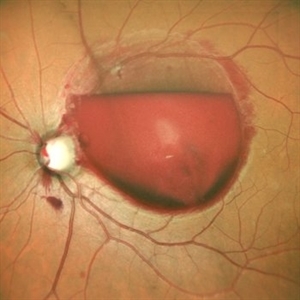

Subretinal Bleed

Jul 12 2022 by Akansha Sharma

A 60 YEAR OLD FEMALE PRESENTED WITH COUNTING FINGERS VISION FROM A SUB-RETINAL HEMORRHAGE AT THE MACULA. OCT SHOWS VARIABLE SUB -RETINAL FLUID. PARS PLANA VITRECTOMY WITH DRAINAGE OF THE SUB-RETINAL BLOOD WAS PERFORMED. POST-OPERATIVE OCT SHOWS NO SUB-RETINAL FLUID WITH VARIABLE OUTER RETINAL CYSTIC CHANGES AND VISUAL ACUITY IMPROVING TO 20/120.

Photographer: Dr. Akansha Sharma-Retina Foundation, Ahmedabad

Condition/keywords: subretinal hemorrhage, subretinal blood